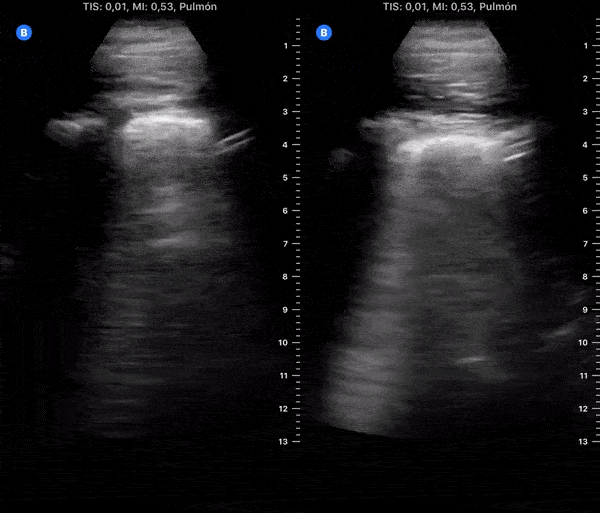

COVID 19 Lung US Disease Progression - Day 7

Day 7 after #COVID diagnosis. Cough & weakness got worse (again), still no dyspnea. No fever. SpO2 96%. #POCUS update: similar to yesterday - thick pleural line, b-lines & consolidations tend to resolve. @yaletung